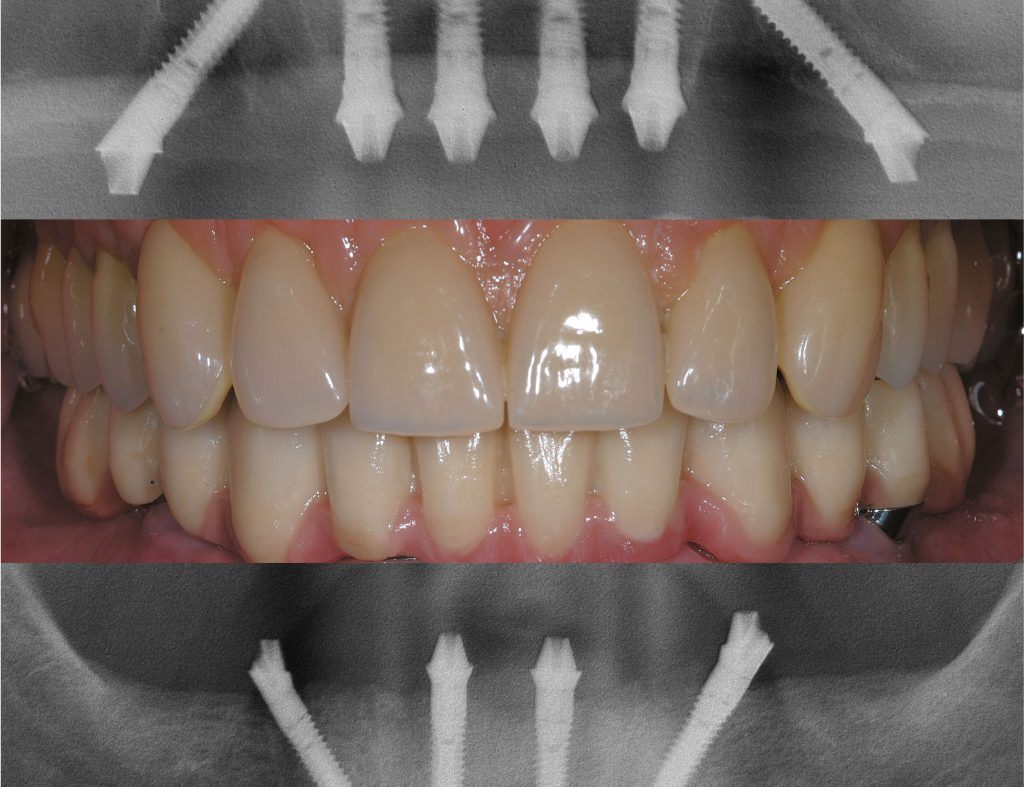

Darstellung der Implantate von Sky fast and fixed mit einem Röntgenbild

Therapie: Am Behandlungstag werden die Implantate an den zuvor geplanten Positionen im Kieferknochen eingesetzt. Nach dem Einsetzen erfolgen eine Bissregistrierung und eine Abformung, die dem Zahntechniker die Grundlage für die Brückenkonstruktion liefern. Dank dieser Konstruktion ist keine Vollprothese mehr erforderlich.

Sobald Ihr Zahnersatz von unserem hauseigenen Dentallabor fertiggestellt wurde, wird er auf den zuvor eingebrachten Implantaten fest verschraubt. Dies gibt Ihnen das Gefühl von festen, eigenen Zähnen zurück und steigert Ihre Lebensqualität mit einem strahlenden Lächeln.